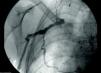

The procedure was performed under general anesthesia. A longitudinal incision was made in the right groin, a few cm below the inguinal ligament, enabling visualization of the femoral vein (Figure 4). The vein was punctured using the Seldinger technique, and a guide wire was inserted into the vessel, followed by a 7F introducer (Medtronic Inc., Minneapolis, MN). A 5.7F, 85-cm bipolar active-fixation lead (CapSureFix® Novus 4076-85, Medtronic Inc., Minneapolis, MN) was inserted through the introducer previously positioned in apical-septal position.

Correct positioning of the lead in apical position was confirmed by detection of a current of injury of >4 mV on the right ventricular electrogram.

Satisfactory sensing and stimulation thresholds were obtained (sensing 6.6 mV; impedance 630 Ω; threshold 0.5 mV at 0.4 ms), and the introducer was withdrawn, leaving a sufficiently large loop in the lead to avoid dislodgement by stretching. The lead was fixed with non-absorbable sutures to the underlying muscle using the suture anchors. A PPM pocket was constructed in the subcutaneous tissue of the lower abdominis muscle on the same side, through a second incision sufficiently above the inguinal ligament to avoid local discomfort (Figure 5). The lead was then tunneled subcutaneously over the femoral ligament from the infrainguinal incision to the pocket, and connected to the pacemaker battery (Adapta, Medtronic Inc.).